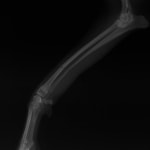

ペルシャ猫 11ヶ月齢 雄

他院にて左大腿骨遠位の成長板骨折(salter-harrisⅠ型)が認められており、治療相談を目的として来院。当院にて、キルシュナーワイヤーを用いたピンニングにより骨折部位の整復を行いました。術後の経過は良好で、現在も経過観察中です。

術前レントゲン